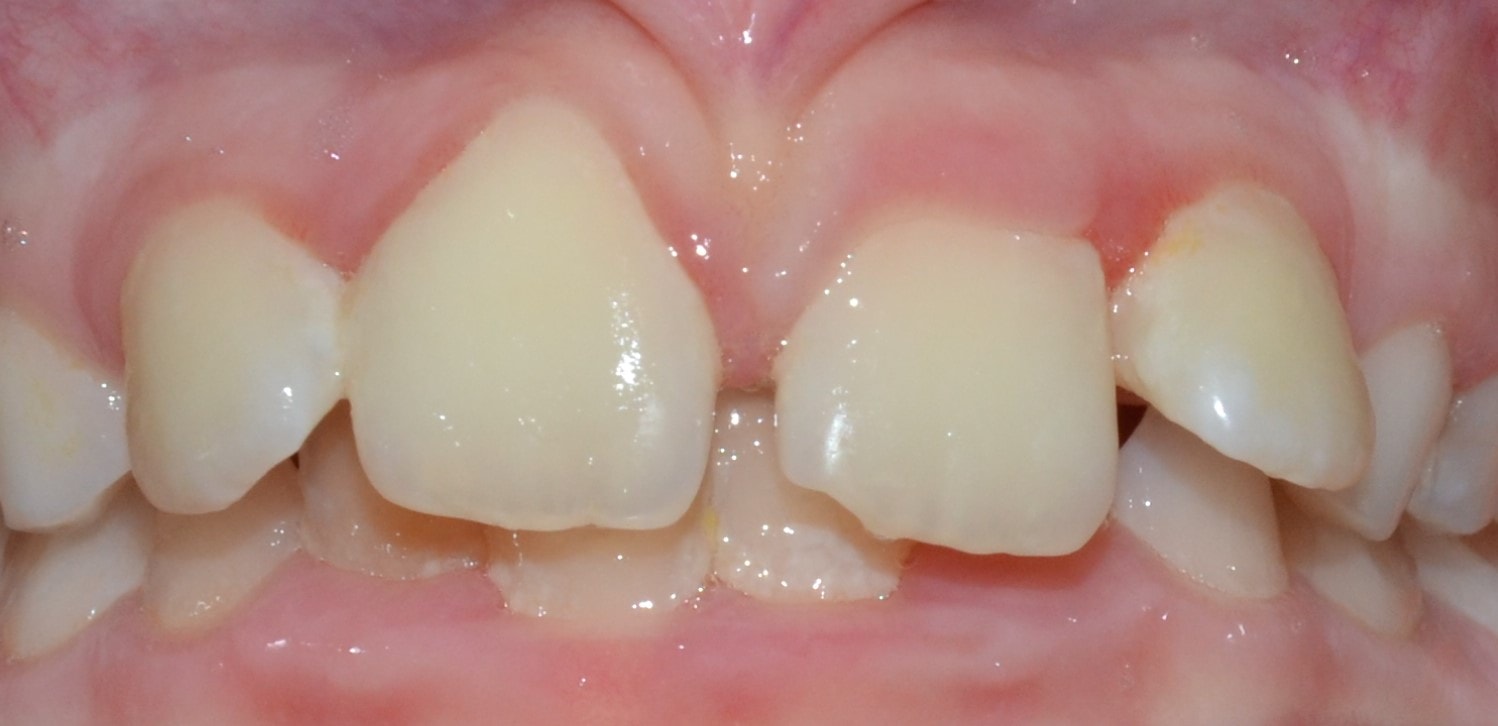

Diasthema medianum

Gyakori fogszabályozási probléma a két felső nagymetsző között jelentkező rés. Ellátását számos faktor befolyásolja. A vegyesfogazatban gyakori, legtöbbször normális jelenség, ami később spontán záródhat, ezért túlságosan korai ellátását semmi sem indokolja. Diasthemat eredményezhet például kifejezett ajakfék, számfeletti fog, kismetsző csírahiány.